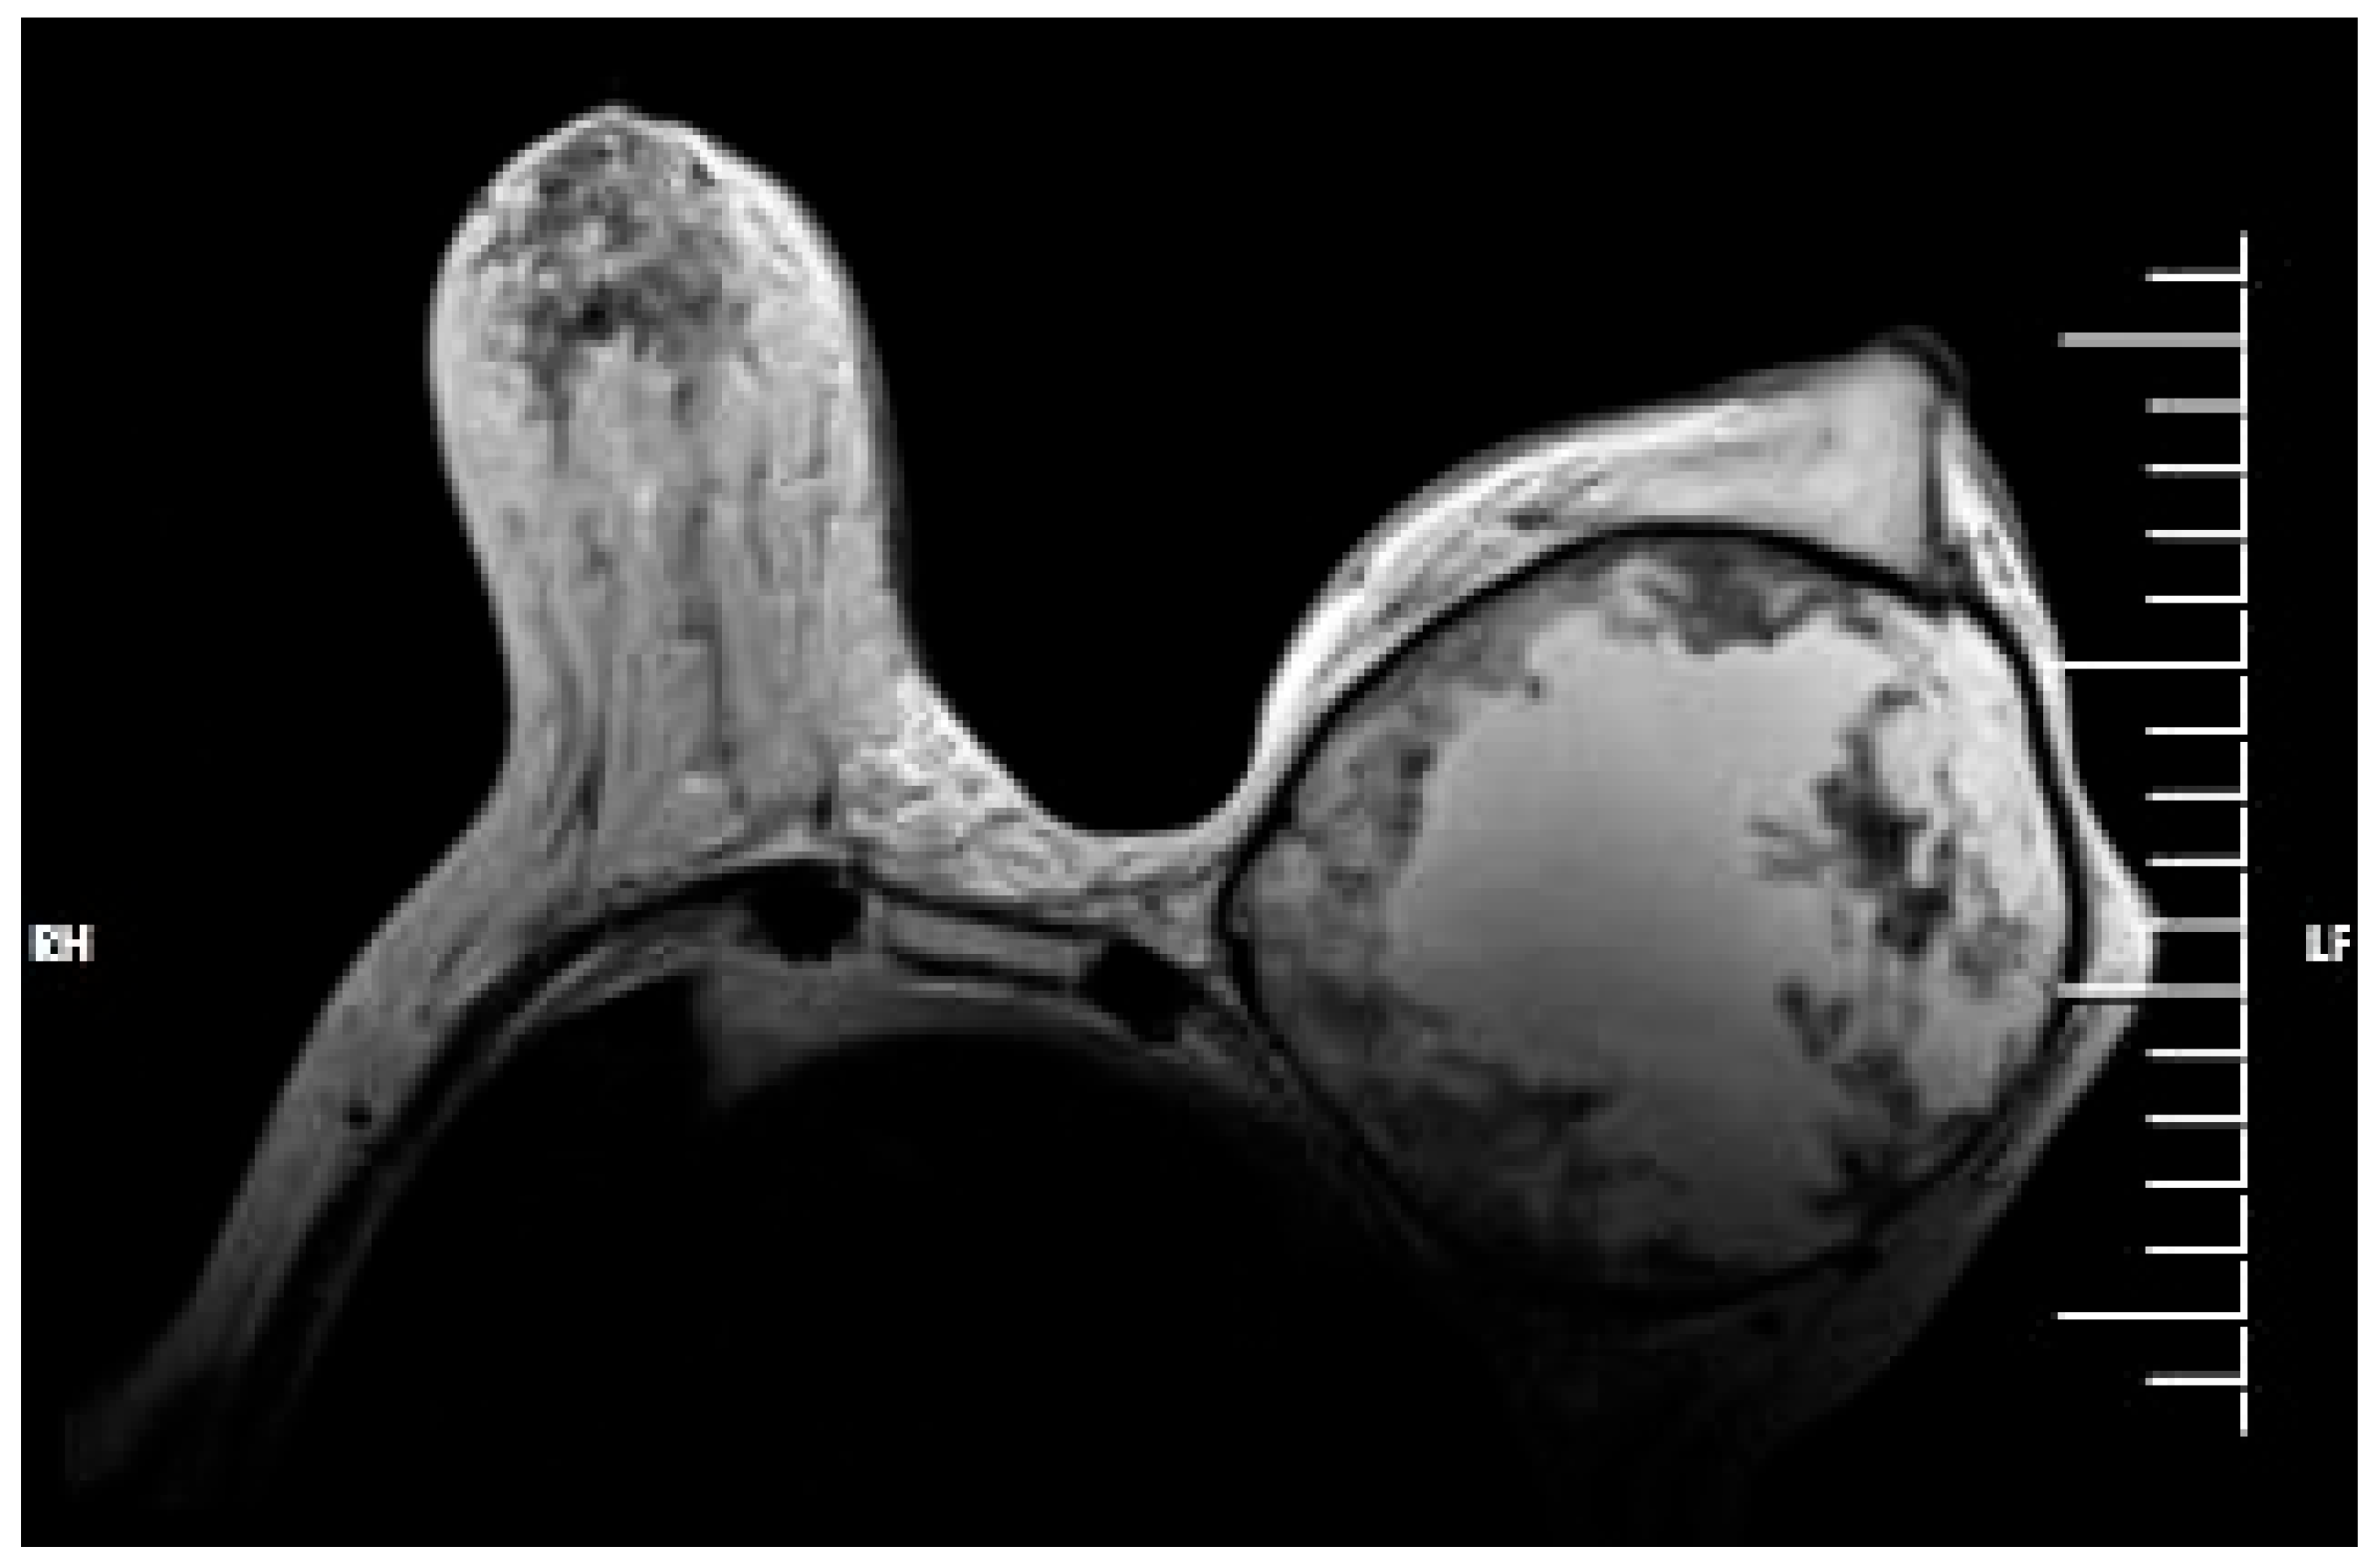

2. Case Report